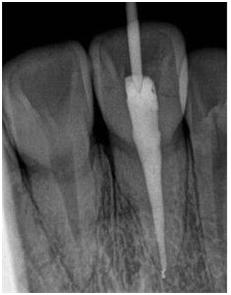

重点来了,来看看做得好的根管长什么样:

片子上可以很清晰地看出根管里面均匀地充满了不透光的材料(片子上白色的),把中空的根管恰好填满,看着就非常舒服~